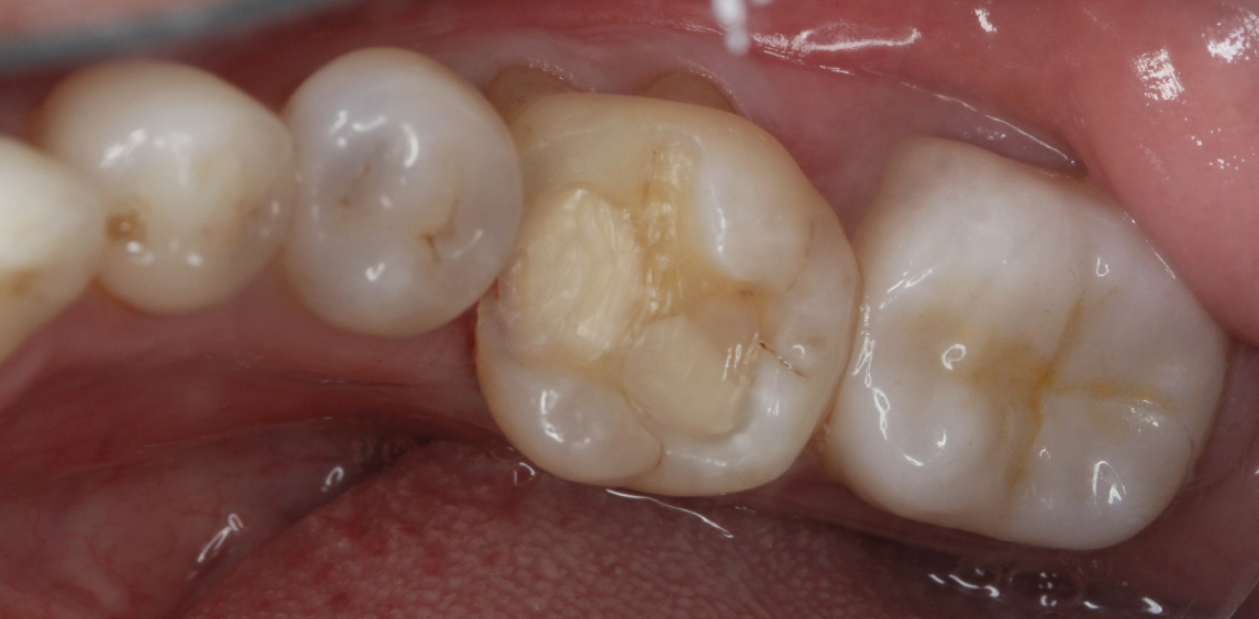

嵌体修复是一种精准的修复方式,特别适合像患者这样龋坏较深但无需根管治疗的情况。该患者选择了西诺德全瓷嵌体修复,去龋坏,IROOT-BP间接盖髓+光固化玻璃离子+3M流动树脂垫底。基牙预备,排龈,精修,然后CEREC扫描,获取牙齿模型,定制出与缺损部位完全匹配的陶瓷嵌体。嵌体制作完成后,医生将其粘接固定在牙齿上,恢复了牙齿的形态和功能。